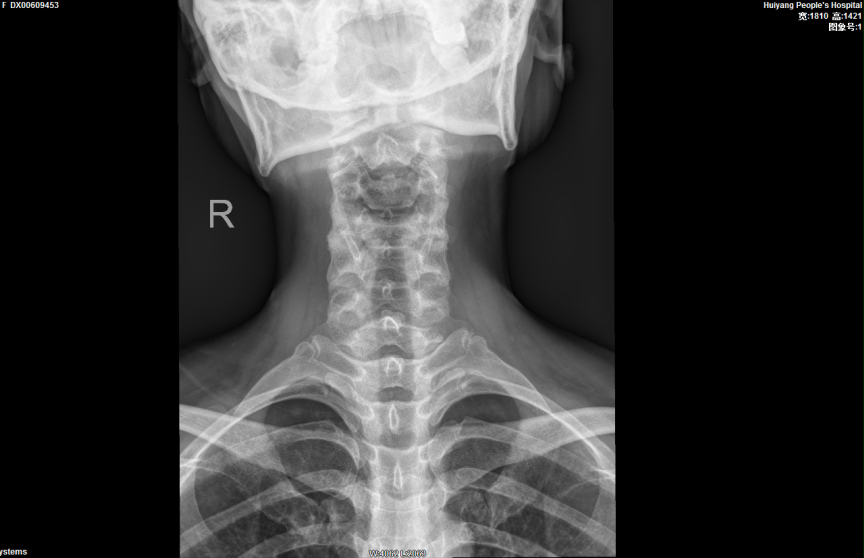

完善相關檢查後(hòu), 報告提示患者的頸椎生理曲度變直,序列如常。C2-7椎體邊緣可見不同程度骨質變尖、突起(qǐ)。C2/3椎間隙明顯變窄,呈前窄後(hòu)寬改變;餘椎間隙未見明顯變窄。項韌帶未見鈣化。寰樞關節開(kāi)口位見雙側不對(duì)稱,左側較右側爲寬(左側6mm,右側3mm),關節面(miàn)光整,寰椎、樞椎骨質未見明顯異常。周圍軟組織未見異常密度。